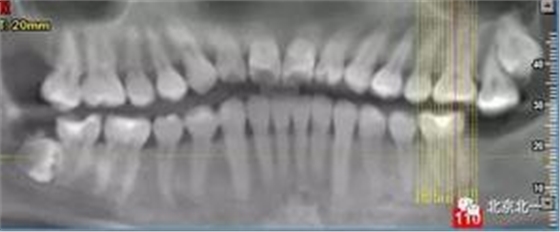

病例資料:一般情況,患者女性,28歲, 主訴:要求拔右側下頜智齒,檢查:右側下頜第三磨牙未見萌出, 拍片如圖。

圖一:CBCT顯示右側下頜水平骨埋伏牙,牙冠距離下牙槽神經管接近。